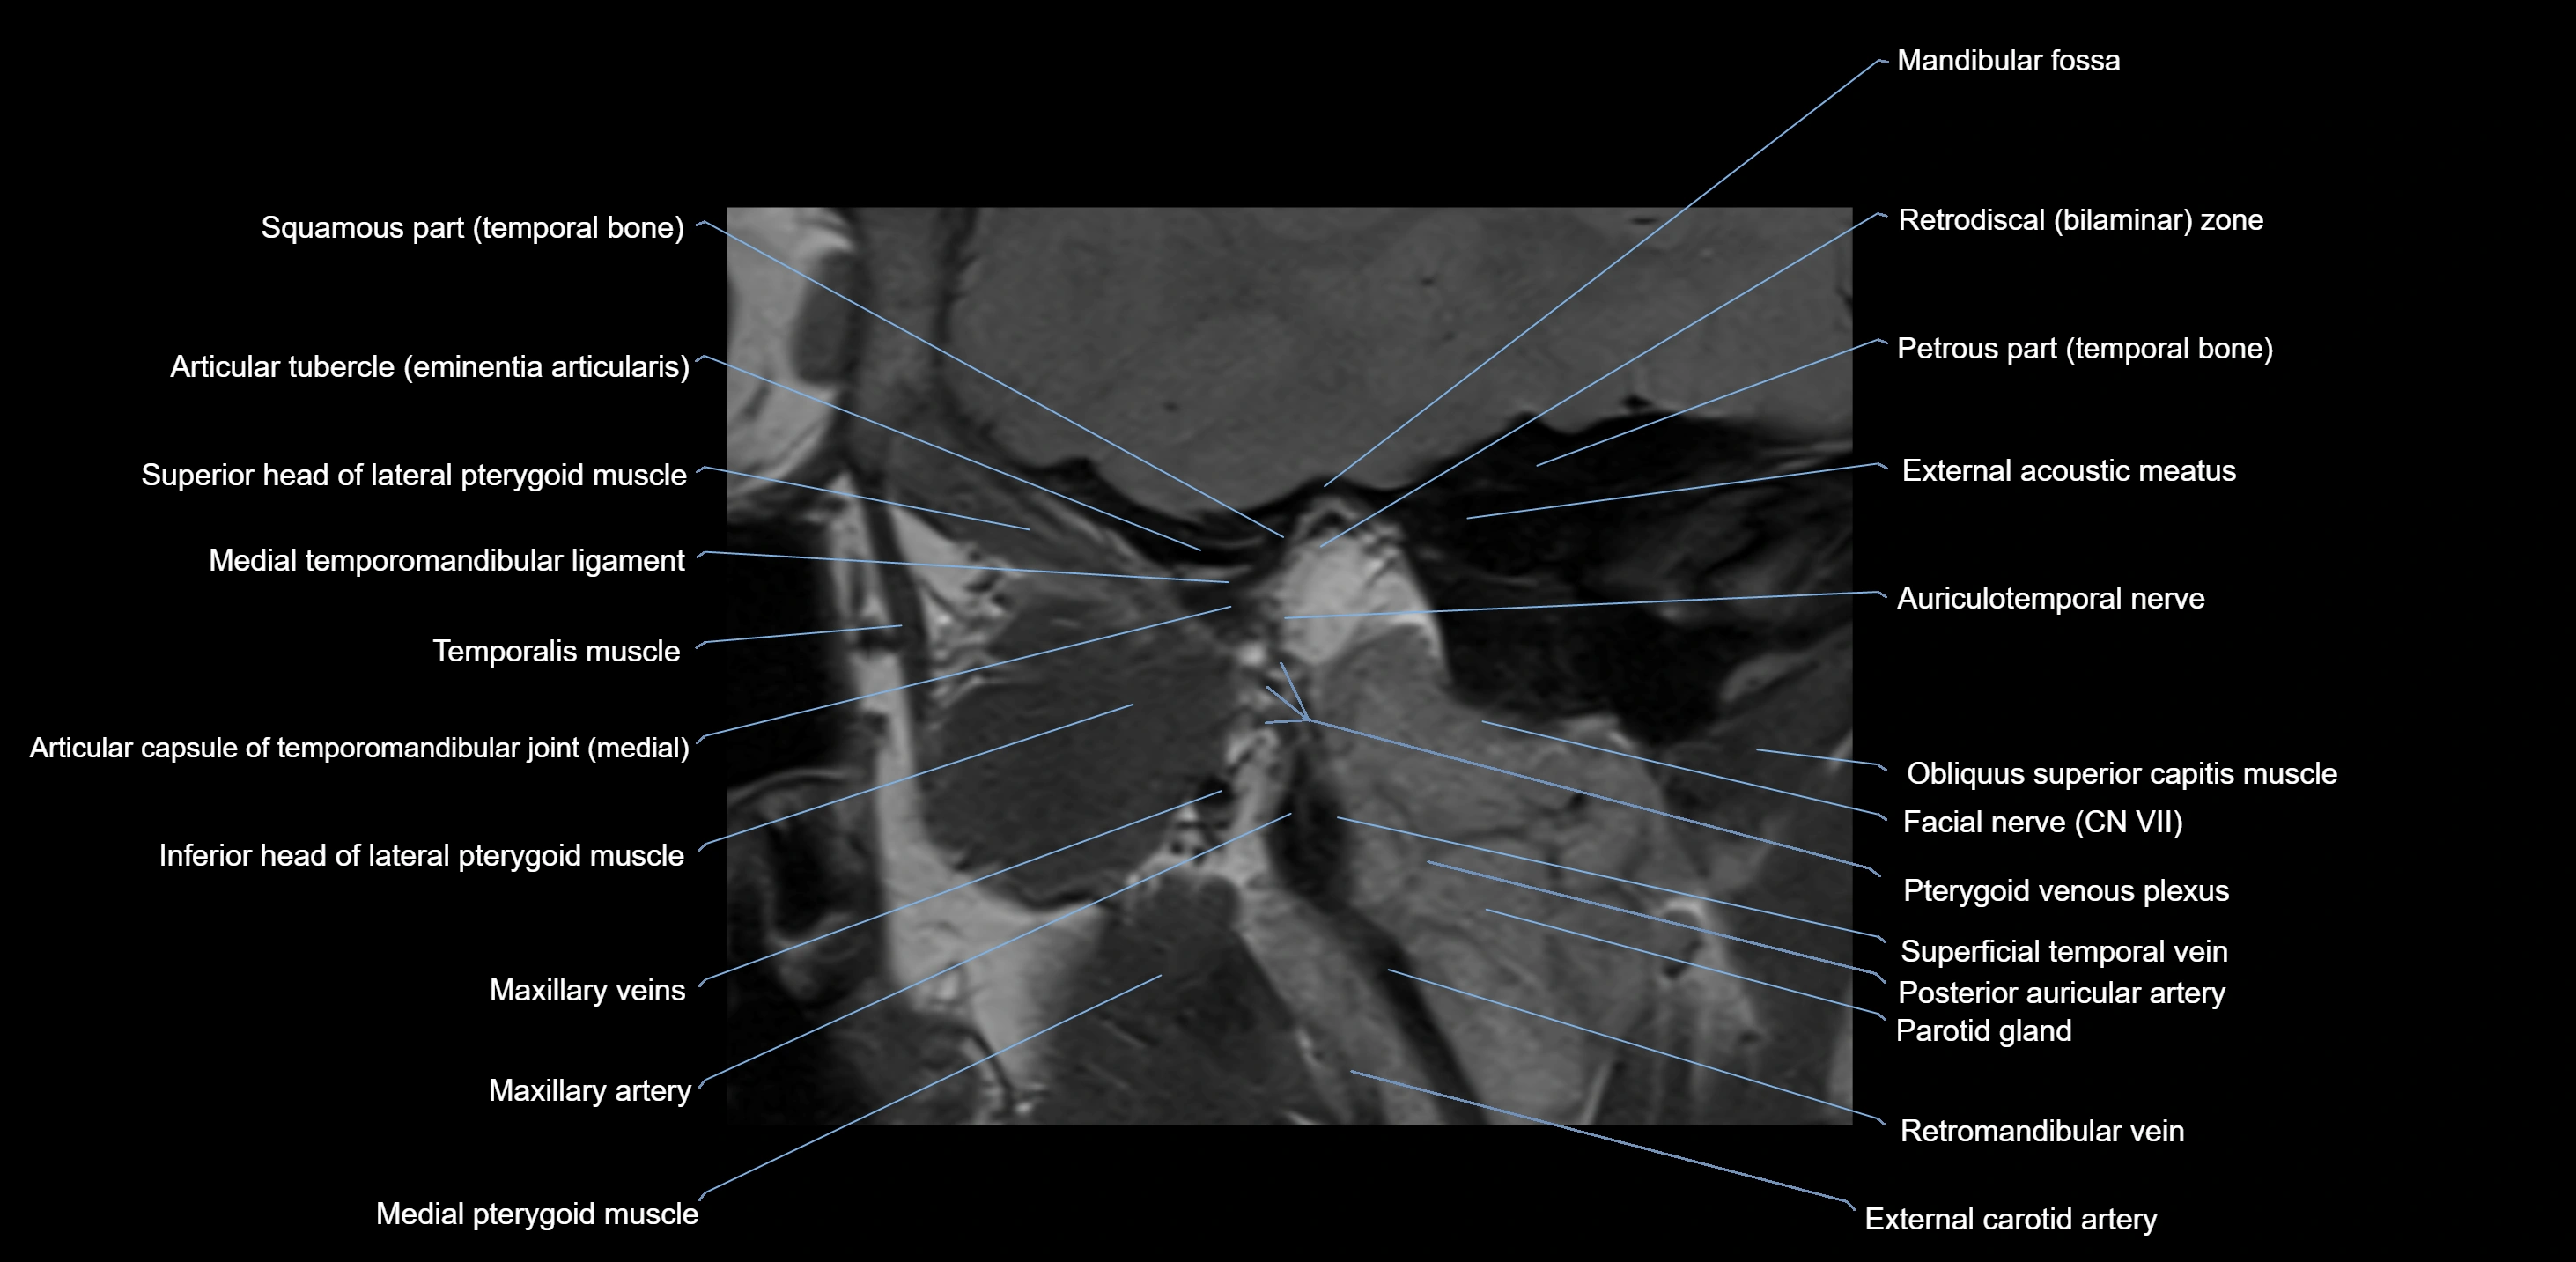

MRI appearance

T1-weighted images:

• Cortical bone: Low signal intensity

• Cancellous marrow: Intermediate to high signal depending on fatty content

• Teeth: Signal void structures

• Adjacent soft tissues: Normal gingiva and oral mucosa signal

T2-weighted images:

• Cortical bone and teeth: Low signal

• Marrow: Intermediate signal